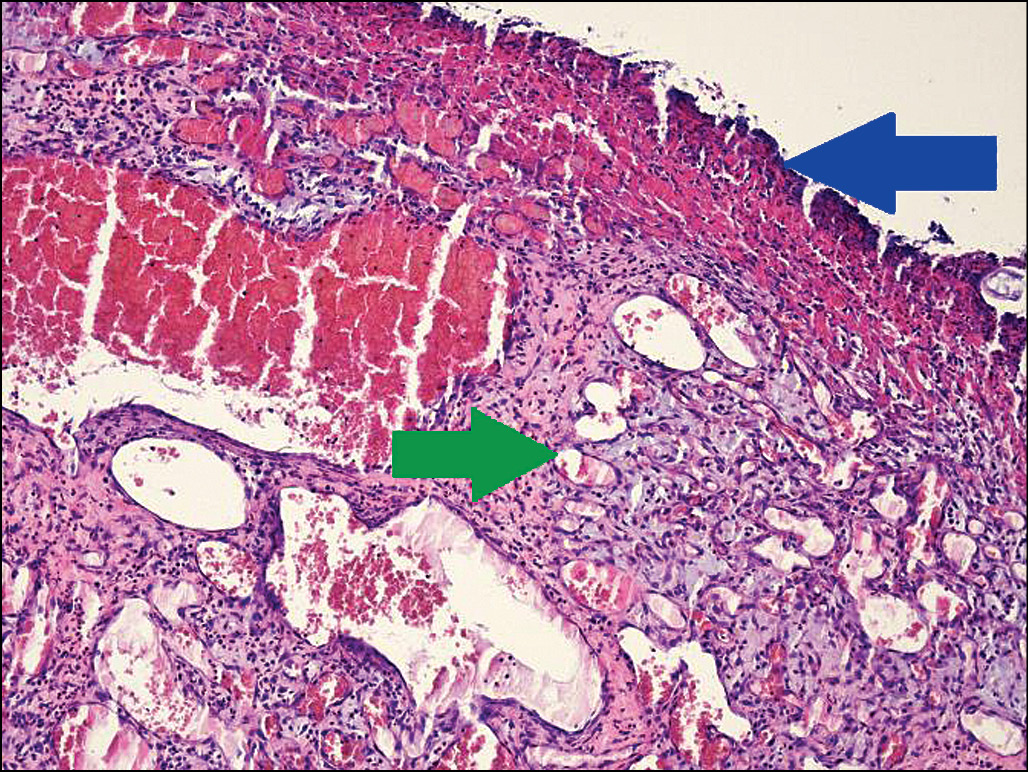

Рис. 2. Гистологический препарат. Опухоль с изъязвленной по- верхностью кожи (синяя стрелка), многодольчатые сосудистые структуры (зелёная стрелка). Окраска гематоксилином и эозином. Ув. 100.

При микроскопическом исследовании опухоль хорошо отграничена от нормальных тканей, эпидермис над опухолью с признаками изъязвления (рис. 2). Основа опухоли представлена пролиферирующими мелкими капиллярами, имеющими вид многодольчатых структур, окружённых фиброзной или несколько отёчной стромой (рис. 3). Каждая долька гемангиомы образована крупным кровеносным сосудом. Клетки хронического и острого воспаления распределены в опухоли, преимущественно в её поверхностных отделах. Заключение: дольчатая капиллярная гемангиома (пиогенная гранулёма) кожи (см. рис. 3).